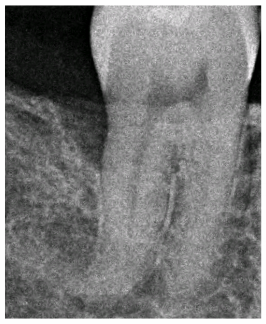

Before After

Before and after X-rays demonstrating a healthy bony refill on the distal of the lower molar after only one session of Perioscopy. Bone loss on the back of the last molar is a common problem occurring after extraction of some wisdom teeth. With the help of Perioscopy we can now save more teeth than ever before!